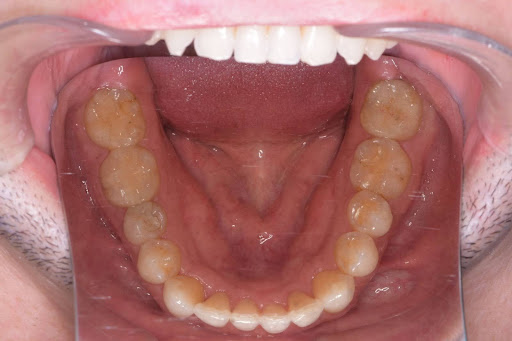

以下の症例写真例は、40代男性の症例です。

前歯のがたつきを改善するためにインビザラインによる矯正とセラミックインレー、根管治療を行い、金属を使わないメタルフリー治療を実施しました。

見た目と機能の両面で大きく改善している様子がわかります。

<Before>